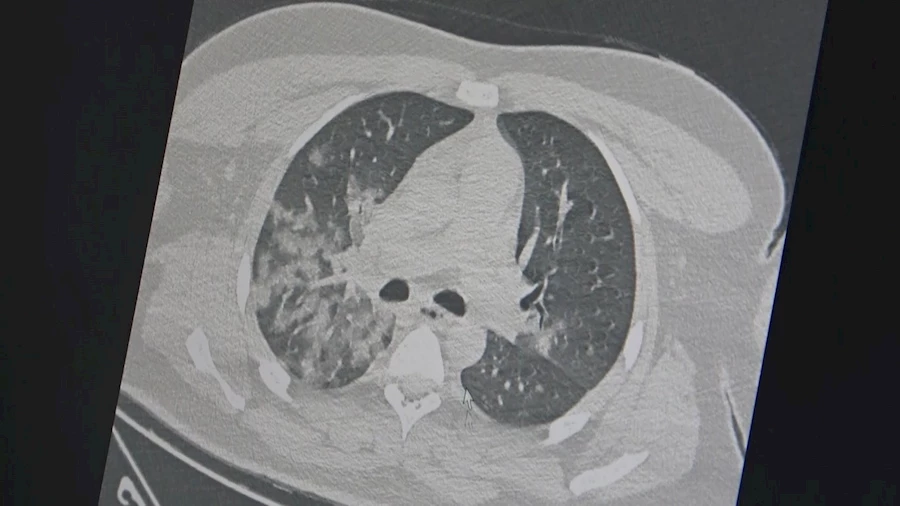

Kovid-19 salgını sonrası özellikle acil servislerde genç hastalarda ani ölümle sonuçlanan akciğer ve kalp/damar hastalıklarında ciddi artış olduğunu ifade eden Göğüs Hastalıkları Uzmanı Prof. Dr. Şevket Özkaya, açıklamalarda bulundu. Özkaya, "Tüm dünyada en çok sorulan soru, bu artan ani ölümlerin sebebi kovid-19 aşıları mı yoksa korona virüsünün etkileri mi? Bu soru İngiltere’de 46 milyon kişi üzerinde yapılan bir araştırma ile netleşti. Kovid-19 aşılarının damar tıkanıklığı sonucu kalp krizi ve inme riskini azalttığını bildirildi. Vücudumuzda damar tıkanıklığı gelişmesinde ve akciğer, kalp ve beyin damarlarında ölümle sonuçlanan olaylara neden olan 3 temel faktör vardır. Damar iç duvarında (endotel) hasar; ameliyat, hastalık veya uzun süre seyahat sebebiyle vücudumuzun hareketsiz kalması, pıhtılaşmaya yatkınlık yapan genetik ve ilaç kullanımı (doğum kontrol hapları vb). Bu 3 faktörden en önemlisi olan damar iç duvarı (endotel) hasarı olup, kovid-19 virüsü ile enfekte olan bir kişide virüs yüküne bağlı gelişen özellikle ’sitokin’ fırtınası başta olmak üzere, kan plazmasının toksik ve tahrip edici damar iç duvarında ciddi hasar yapıyor, pıhtı oluşumunun ilk aşaması gerçekleşiyor. Ayrıca hastalık veya uzun süre seyahat sebebiyle vücudumuzun hareketsiz kalması ile pıhtı oluşumuna neden oluyor ve ölümcül sonuçlar ile karşılaşıyoruz. Özellikle gençlerin kovid-19 sonrası bozulmuş damar yapısı, ağır egzersiz ve spor ile ölümcül kalp krizlerine neden oluyor" diye konuştu.

Özkaya şunları söyledi: "Aşılar özellikle salgın döneminde insan vücudundaki virüs yükünü azaltarak, hem hastalığın ağır geçirilmesine hem de kan plazmasının damar iç duvarındaki bu harap edici etkisini azaltıyor. Buna bağlı damar tıkanıklıklarını da azalttığı ve akciğer, kalp ve beyin damarlarındaki ölümcül tıkanıklarını da azalttığını düşünüyoruz. Sonuç olarak, ani artan genç ölümlerinden kovid-19 aşıları değil, kovid-19 virüsünün damar hasarına yaptığı hasar nedeniyle olduğu kanıtlanmış oldu" şeklinde konuştu.